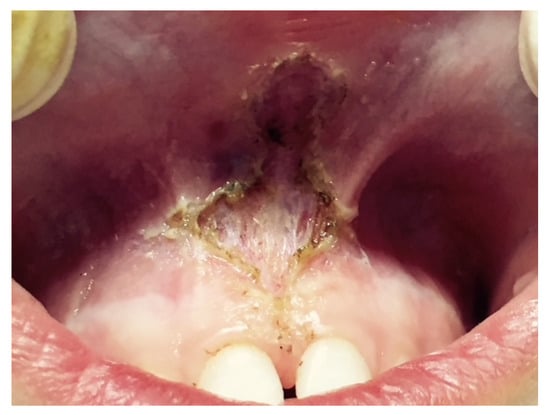

Classical frenectomy/V-shaped Archer/diamond-shaped incision: devised by Archer (1961) and Kruger (1964). The cold blade procedure is the traditional technique and involves a V-shaped incision along the edges of the frenulum, removal of the coronal insertion of the frenulum with subsequent apical repositioning. The periosteal fibres are then cut horizontally and vertically, and the wound is closed with sutures. This technique involves more side effects because it produces the development of scar tissue with possible periodontal repercussions until the disappearance of the interincisive papilla (Figure 3).

Figure 3.

Frenectomy with traditional and V-shaped surgery: (A) Transpapillary frenulum; (B) two paramedian vertical incisions are drawn parallel to the sides of the frenulum up to the retroincisive papilla, where they connect with a horizontal cut; the frenulum is raised and the periosteum is exposed; (C) the margins are sutured along the midline, not involving the adherent gingiva; and periodontal wrap and healing by second intention.